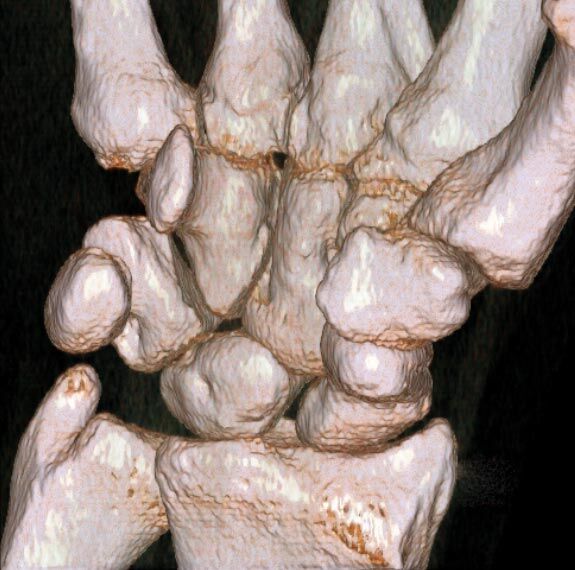

Extremitäten

• bei komplizierten Frakturen z. B. in der Nähe von Gelenken oder im Bereich der Handwurzel und Fußwurzel